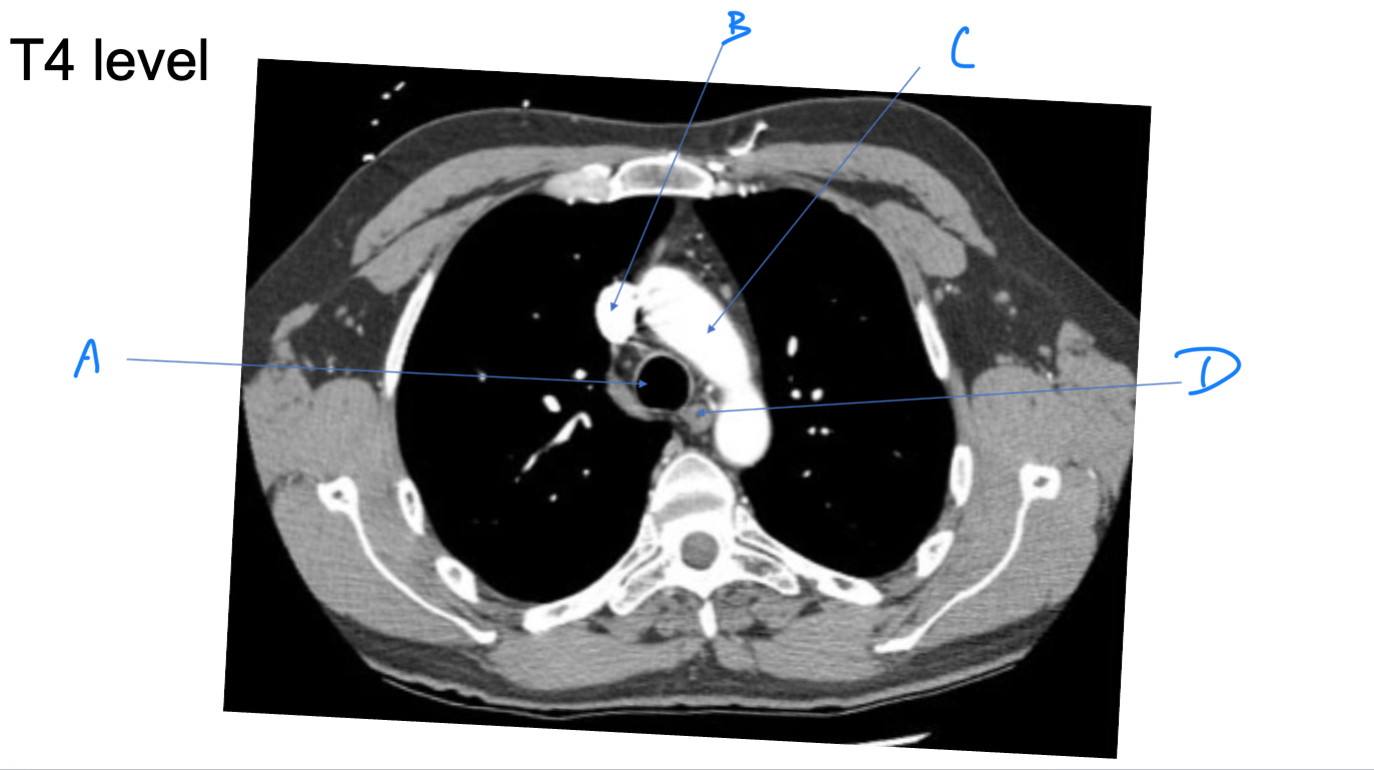

Esophagus

A. Identify

Trachea

B. Identify

R Brachiocephalic v.

C. Identify

Brachiocephalic trunk

D. Identify

L CCA

E. Identify

L Brachiocephalic v.

F. Identify

L Subclavian a.

G. Identify

Trachea

A. Identify

Superior vena cava (SVC)

B. Identify

Arch of aorta

C. Identify

Esophagus

D. Identify